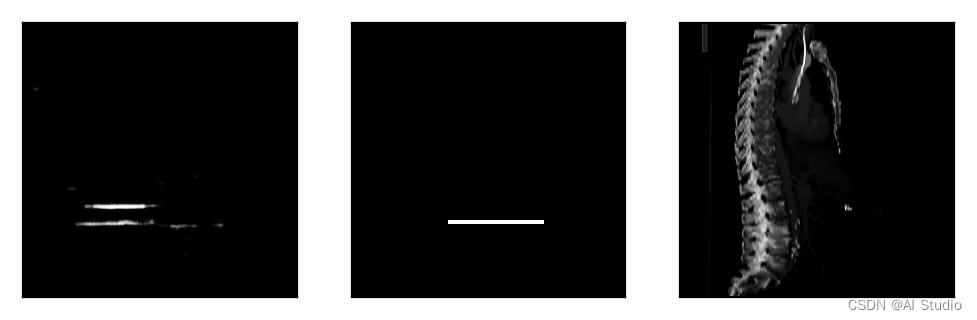

plt.figure(figsize=(6, 18))

plt.subplot(1,3,1),plt.xticks([]),plt.yticks([]),plt.imshow(predict,cmap='gray')

plt.subplot(1,3,2),plt.xticks([]),plt.yticks([]),plt.imshow(label,cmap='gray')

plt.subplot(1,3,3),plt.xticks([]),plt.yticks([]),plt.imshow(inputs,cmap='gray')

plt.show()

index_predict= np.argmax(np.max(predict,1))+3

index_label = np.argmax(np.max(label,1))

print('真实位置:',index_label,'预测位置:',index_predict)

Error_mean.append(np.abs(index_label-index_predict))

Error_std.append(index_label-index_predict)

break

print("第{}个模型测试集平均定位误差为:{:.2f},定位误差标准差为:{:.2f}".format(K,np.mean(Error_mean),np.std(Error_std)))